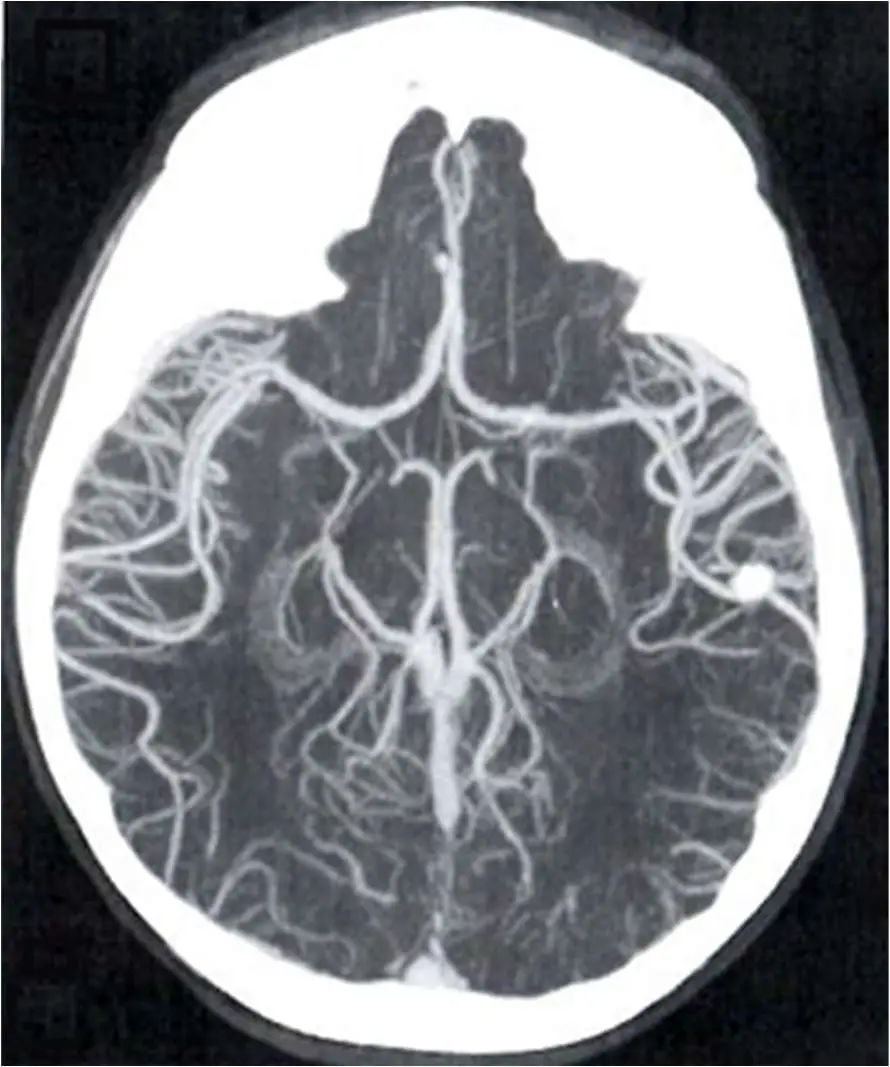

圖片顯示為一張腦部的軸切面(Axial view)影像,可觀察到以下幾個關鍵特徵:

- 高信號/高密度結構突出:影像中頭部外圍的骨骼與腦部血管(如威利氏環、大腦中動脈 MCA 等分支)呈現極高的亮度。

- 結構重疊(Overlapping)與二維投影:不同深度的血管網絡在同一個平面上重疊顯示,使整體影像看起來類似傳統的血管攝影(Angiography),而非單一切層的斷面解剖。

- 缺乏深度感與立體陰影:雖然能看到豐富交織的血管樹,但影像呈現為「扁平」的 2D 投影,沒有 3D 立體模型特有的光影變化、透明度或立體深度感(Depth perception)。

- 背景組織抑制:周圍的腦實質(brain parenchyma)呈現較暗的灰色,與高亮度的血管及骨骼形成強烈對比。 以上特徵為「最大強度投影(Maximum Intensity Projection, MIP)」技術的典型影像表現。

- (B) maximum intensity projection(MIP,最大強度投影):運算時沿著使用者的視線方向(ray path),僅選取穿過體積數據中「強度(CT number 或訊號)最大」的體素(voxel)來成像。此技術能有效凸顯含對比劑的血管或骨骼,並將不同深度的最高值投射在同一平面上。本題影像即為典型的 MIP 腦血管造影,缺乏深度感但血管對比較高。

正確答案為 (B) maximum intensity projection(MIP)。 由提供的影像可觀察到,血管網絡雖然完整呈現,卻像被「壓扁」投影在一個二維平面上,缺乏 3D 空間的立體陰影與深度感。這正是 MIP 的運算原理:電腦沿著視角方向,只抓取並顯示最大強度的像素(即打入對比劑的血管與骨骼),而忽略並穿透較低強度的組織(如腦組織),因此被廣泛應用於 CT 血管攝影(CTA)及 MR 血管攝影(MRA)的影像呈現。